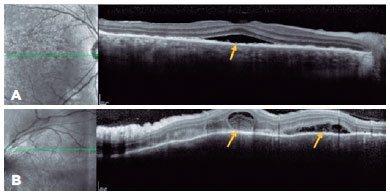

A 43-year-old man presented with low insidious and painless VA in OU. Ophthalmological examination revealed optic disc edema in the OD, and OCT showed SRD involving the subfoveal region (Figure 2A) along with the superior regions of the posterior pole, the latter with septa and fibrinoid material (Figure 2B). On OCT, the OS demonstrated irregularity in the RPE. The patient denied a previous trauma history; however, biomicroscopy revealed a small inferior leukoma with an anterior synechia attached to it. Infectious diseases were ruled out, and in the anamnesis review, the patient recalled having experienced an automobile accident but was unaware of the ocular trauma. Systemic treatment with the oral administration of prednisone (1 mg/kg/day) was initiated in a slowly tapering dosage. The patient had improved VA and fundoscopic findings and was followed up for nearly 1 year without recurrence.